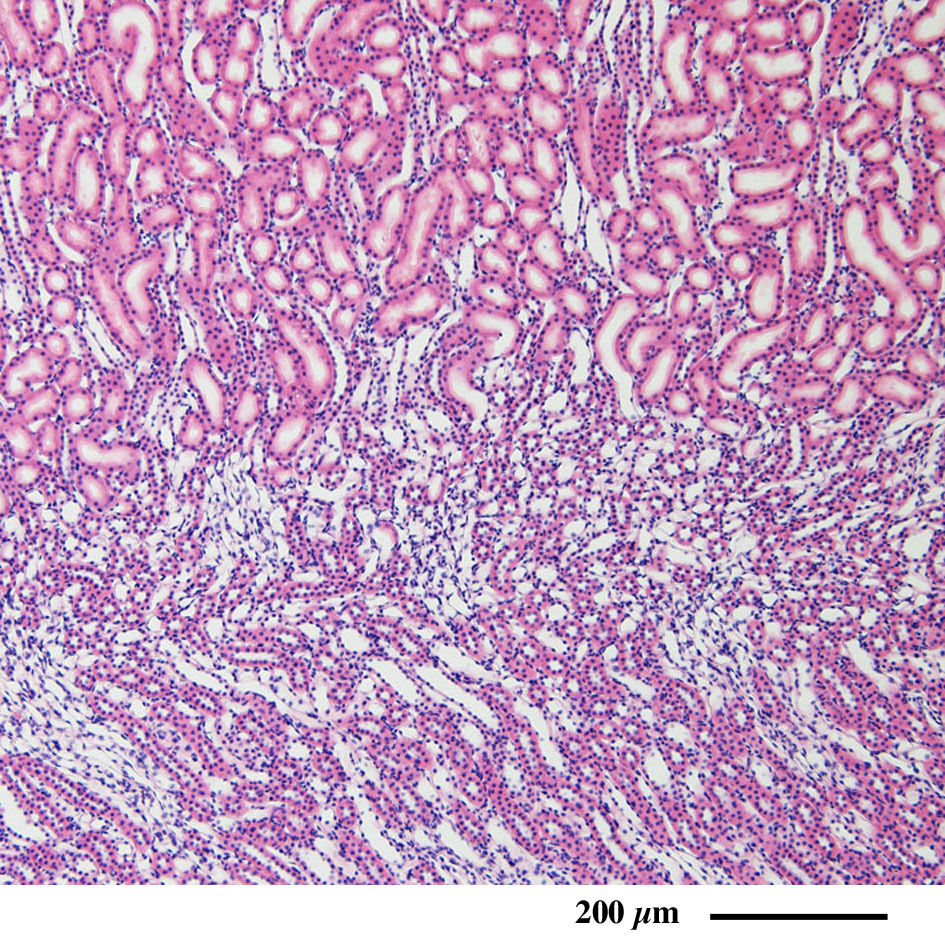

腎 臓(ラット) Kidney ( rat )

パラフィン切片のヘマトキシリン・エオジン染色光学顕微鏡画像

Light microscopic image of paraffin section with hematoxylin & eosin staining

腎皮質の概観

腎髄質の概観